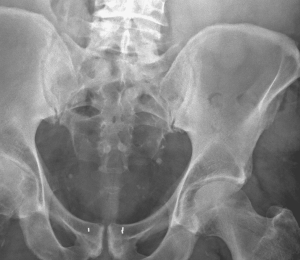

Your X-rays are your personal information and you have a right to view them should you so decide.

At this time, there is no convenient, centralized and practical process to access your X-ray results. However, the information can be accessed via the Internet provided you have the proper accessing credentials which are availabe through your X-ray service office. Remember because these results are your personal information you have a right to it.

Your X-ray service can provide you with Internet access to your X-ray results. Request that they give you “Patient Portal Access Details” whereby you can access and view your x-ray information conveniently, privately and when you want. This is a useful service if you want to examine, review and study your xray information yourself.